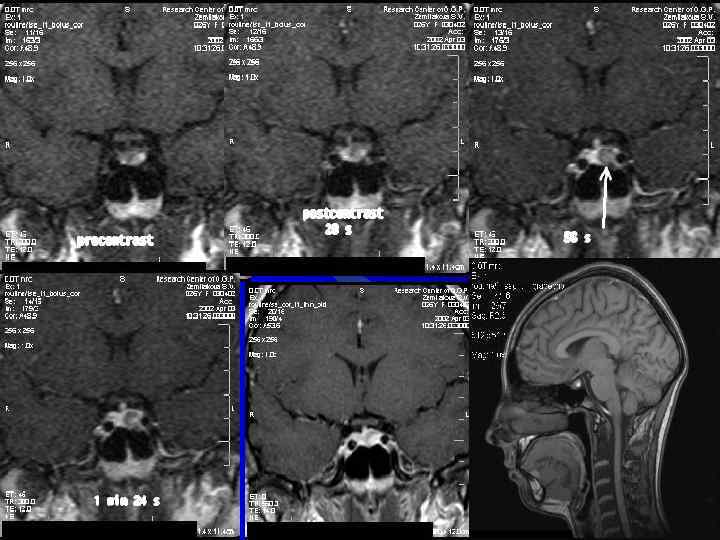

МРТ головного мозга с применением 1, 0 молярного МРКС Анамнез Пациент с неясным диагнозом, находится в неврологическом отделении с периодическими головными болями и высокой температурой. Плановое исследование Задачи исследования Дифференциальный диагноз Диагноз а- при обследовании пациента без использования контрастного вещества определялись 2 образования неясной этиологии б – после в/в введении 1, 0 молярного МРКС рентгенологическая картина соответствует картине множественных абсцессов Комментарии Для неврологов и нейрохирургов очень важно получить информацию по расположению и структуре объемного образования. Применение 1, 0 молярного МРКС позволило четко поставить диф. диагноз и определить тактику лечения А Б